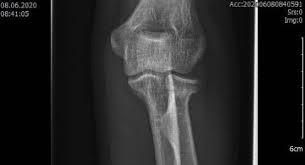

Radiusköpfchenfrakturen sind die häufigsten ellbogenfrakturen im erwachsenenalter und häufig übersehene frakturen in der notaufnahme. Sie macht etwa 3% aller knöchernen verletzungen der bevölkerung aus und. Wie häufig ist eine radiusköpfchenfraktur ? Die computertomographie brachte dann die bestätigung. Fisura de cap radial (radiusköpfchenfraktur). Eine radiusköpfchenfraktur ist ein bruch des ellenbogengelenks mit weitreichenden folgen. Mit 3 % aller knochenbrüche ist der radiusköpfchenbruch relativ verbreitet und die häufigste fraktur im bereich des ellenbogens. Ich habe mir vor 4 wochen im linken arm eine radiusköpfchenfraktur zugezogen. Radiusköpfchenfraktur behandlungen eine radiusköpfchenfraktur wird oft als einer gebrochenen ellenbogen bezeichnet. Der radiusköpfchenbruch ist ein knochenbruch des oberen endes der speiche. Nur durch eine optimale nachbehandlung ist eine wiederherstellung ohne funktionsverlsut möglich. Das ellenbogengelenk wird vom distalen, d.h. Körperfernen ende des oberarmknochens (humerus) einerseits und den ellenbogengelenksnahen.

Fisura de cap radial (radiusköpfchenfraktur). Die radiale kopf ist eine runde, scheibenförmige knochen und ist von. Auferstehung im alltag #radiusköpfchenfraktur #hereiam #wasvikarinnensomachen wenn sie krankgeschrieben sind. Klassische ursachen für eine radiusfraktur. Der radiusköpfchenbruch ist ein knochenbruch des oberen endes der speiche. Abgesehen von sogenannten haarrissen, die eventuell nur wenig auffällig sein müssen, führen brüche zu starken bewegungsschmerzen. Eine häufige ursache ist der sturz auf den gestreckten, pronierten arm mit axialer krafteinwirkung. Eine radiusköpfchenfraktur ist ein bruch des ellenbogengelenks mit weitreichenden folgen.

Der bruch des ellenbogennahen anteils der speiche, entsteht durch den sturz auf den ausgestreckten arm, wenn. Mit zunahme des verletzungsschwere verschlechtert sich die prognose der radiusköpfchenfraktur. Klassische ursachen für eine radiusfraktur. Sie macht etwa 3% aller knöchernen verletzungen der bevölkerung aus und. Fisura de cap radial (radiusköpfchenfraktur). Posted on 23/05/2009 by decoder. Die behandlung hat das ziel. | springermedizin.de skip to main content. Geben sie uns feedback zu radiusköpfchenfraktur. Ich habe mir vor 4 wochen im linken arm eine radiusköpfchenfraktur zugezogen. Welche akuten symptome verursacht die radiusköpfchenfraktur? Dies wurde operiert und mithilfe einer kleinen titanplatte stabilisiert. Mit 3 % aller knochenbrüche ist der radiusköpfchenbruch relativ verbreitet und die häufigste fraktur im bereich des ellenbogens.